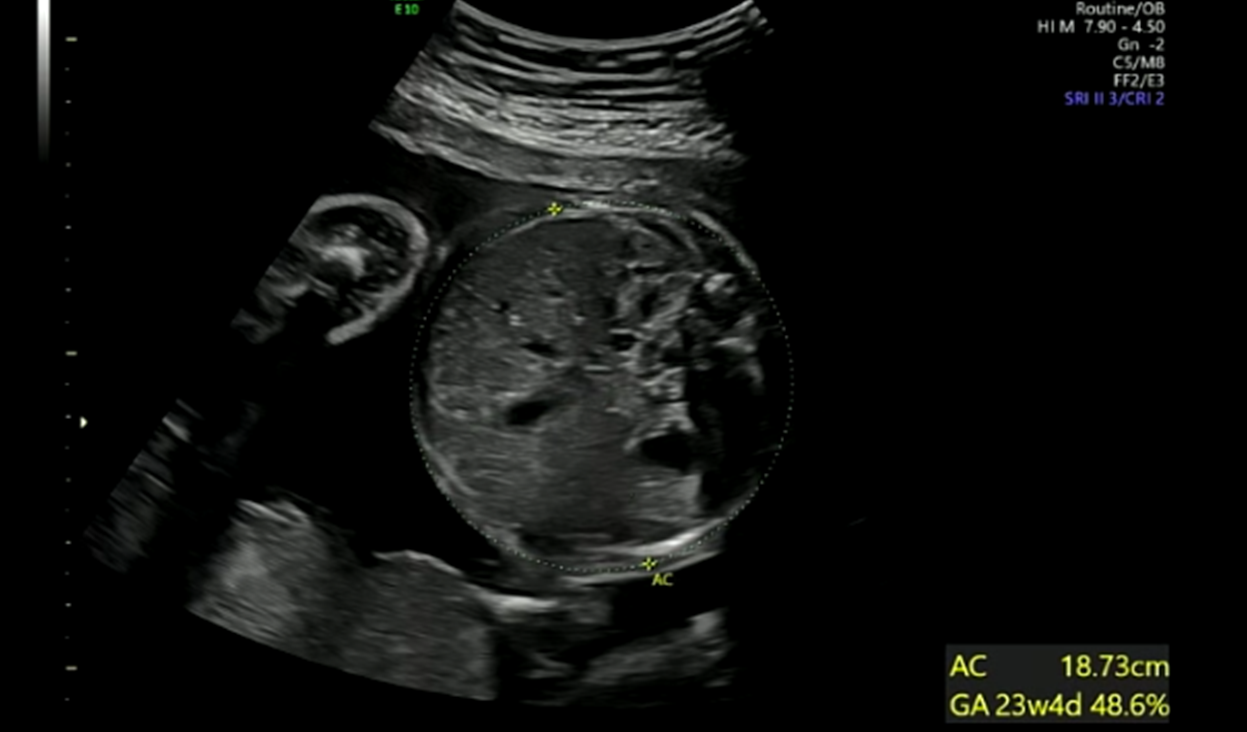

복부

※ 초음파 용어) AC : 복부 둘레

초음파 봐주시는 선생님께서 배도 잘 자라고 있다고 하셨다.